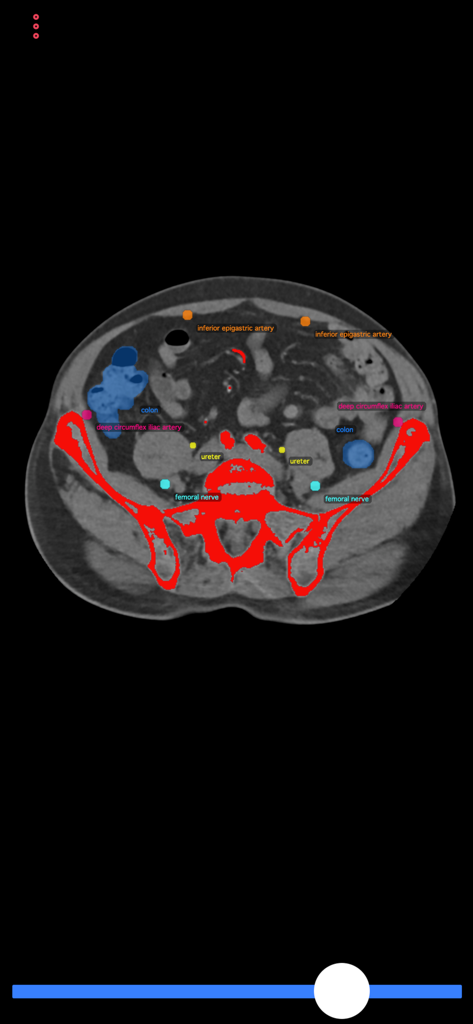

Sección transversal de escaneo TC con etiquetas anatómicas para la guía del procedimiento de biopsia

Sección transversal de escaneo TC en la aplicación Guía de Biopsia con estructuras anatómicas etiquetadas como el colon y las arterias

Identifica Puntos de Referencia Críticos

Minimiza el riesgo del procedimiento visualizando órganos vitales, vasos principales y nervios dentro de secciones transversales detalladas para garantizar una biopsia segura en todo momento.

Esta aplicación consiste en TC (tomografía computarizada) de cuerpo, que demuestra posibles sitios de punción y estructuras anatómicas a evitar durante las intervenciones. El usuario puede desplazarse por las secciones transversales de la TC para encontrar el acceso de punción ideal. Esta aplicación puede guiar a radiólogos intervencionistas y generales, pero también a médicos de atención primaria o a cualquier médico de diagnóstico para realizar una biopsia segura o la colocación de un catéter de drenaje sin lesionar a los pacientes.